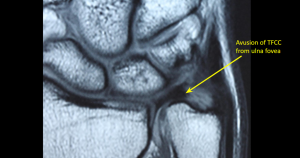

MRI ve artroskopi gibi görüntüleme yöntemleriyle tanı konulabilir.

Üçgen fibrokartilaj kompleksi (TFCC), el bileğinin küçük parmak tarafında (ulnar tarafta) bulunan bir yapı olup, stabilite, amortisör görevi ve hareket kabiliyeti açısından kritik bir rol oynar. TFCC’nin temel bileşenleri şunlardır:

Üçgen Fibrokartilage Kompleksi (TFCC), ön kolun iki ana kemiği olan yarıçapınız ve ulnanız arasındaki bir bölgedir. TFCC, ekstansör karpi ulnaris’e bağlı çeşitli tendonlar, bağlar ve kıkırdaklardan oluşur. Bir nesneyi kavrarken veya ön kolu döndürürken, bilek hareketine yardımcı olur ve ön kol kemiklerini sabitler.

TFCC ayrıca ulnanın distal ucu ile bileğin küçük kemikleri (triquetrum ve lunatum) arasında bir yastık görevi görür. Bazı bireyler, ulnar varyans adı verilen, ulnanın yarıçaptan (ön kolu oluşturan kemikler) daha uzun olduğu konjenital bir anomali nedeniyle TFCC yaralanmalarına yatkındır.